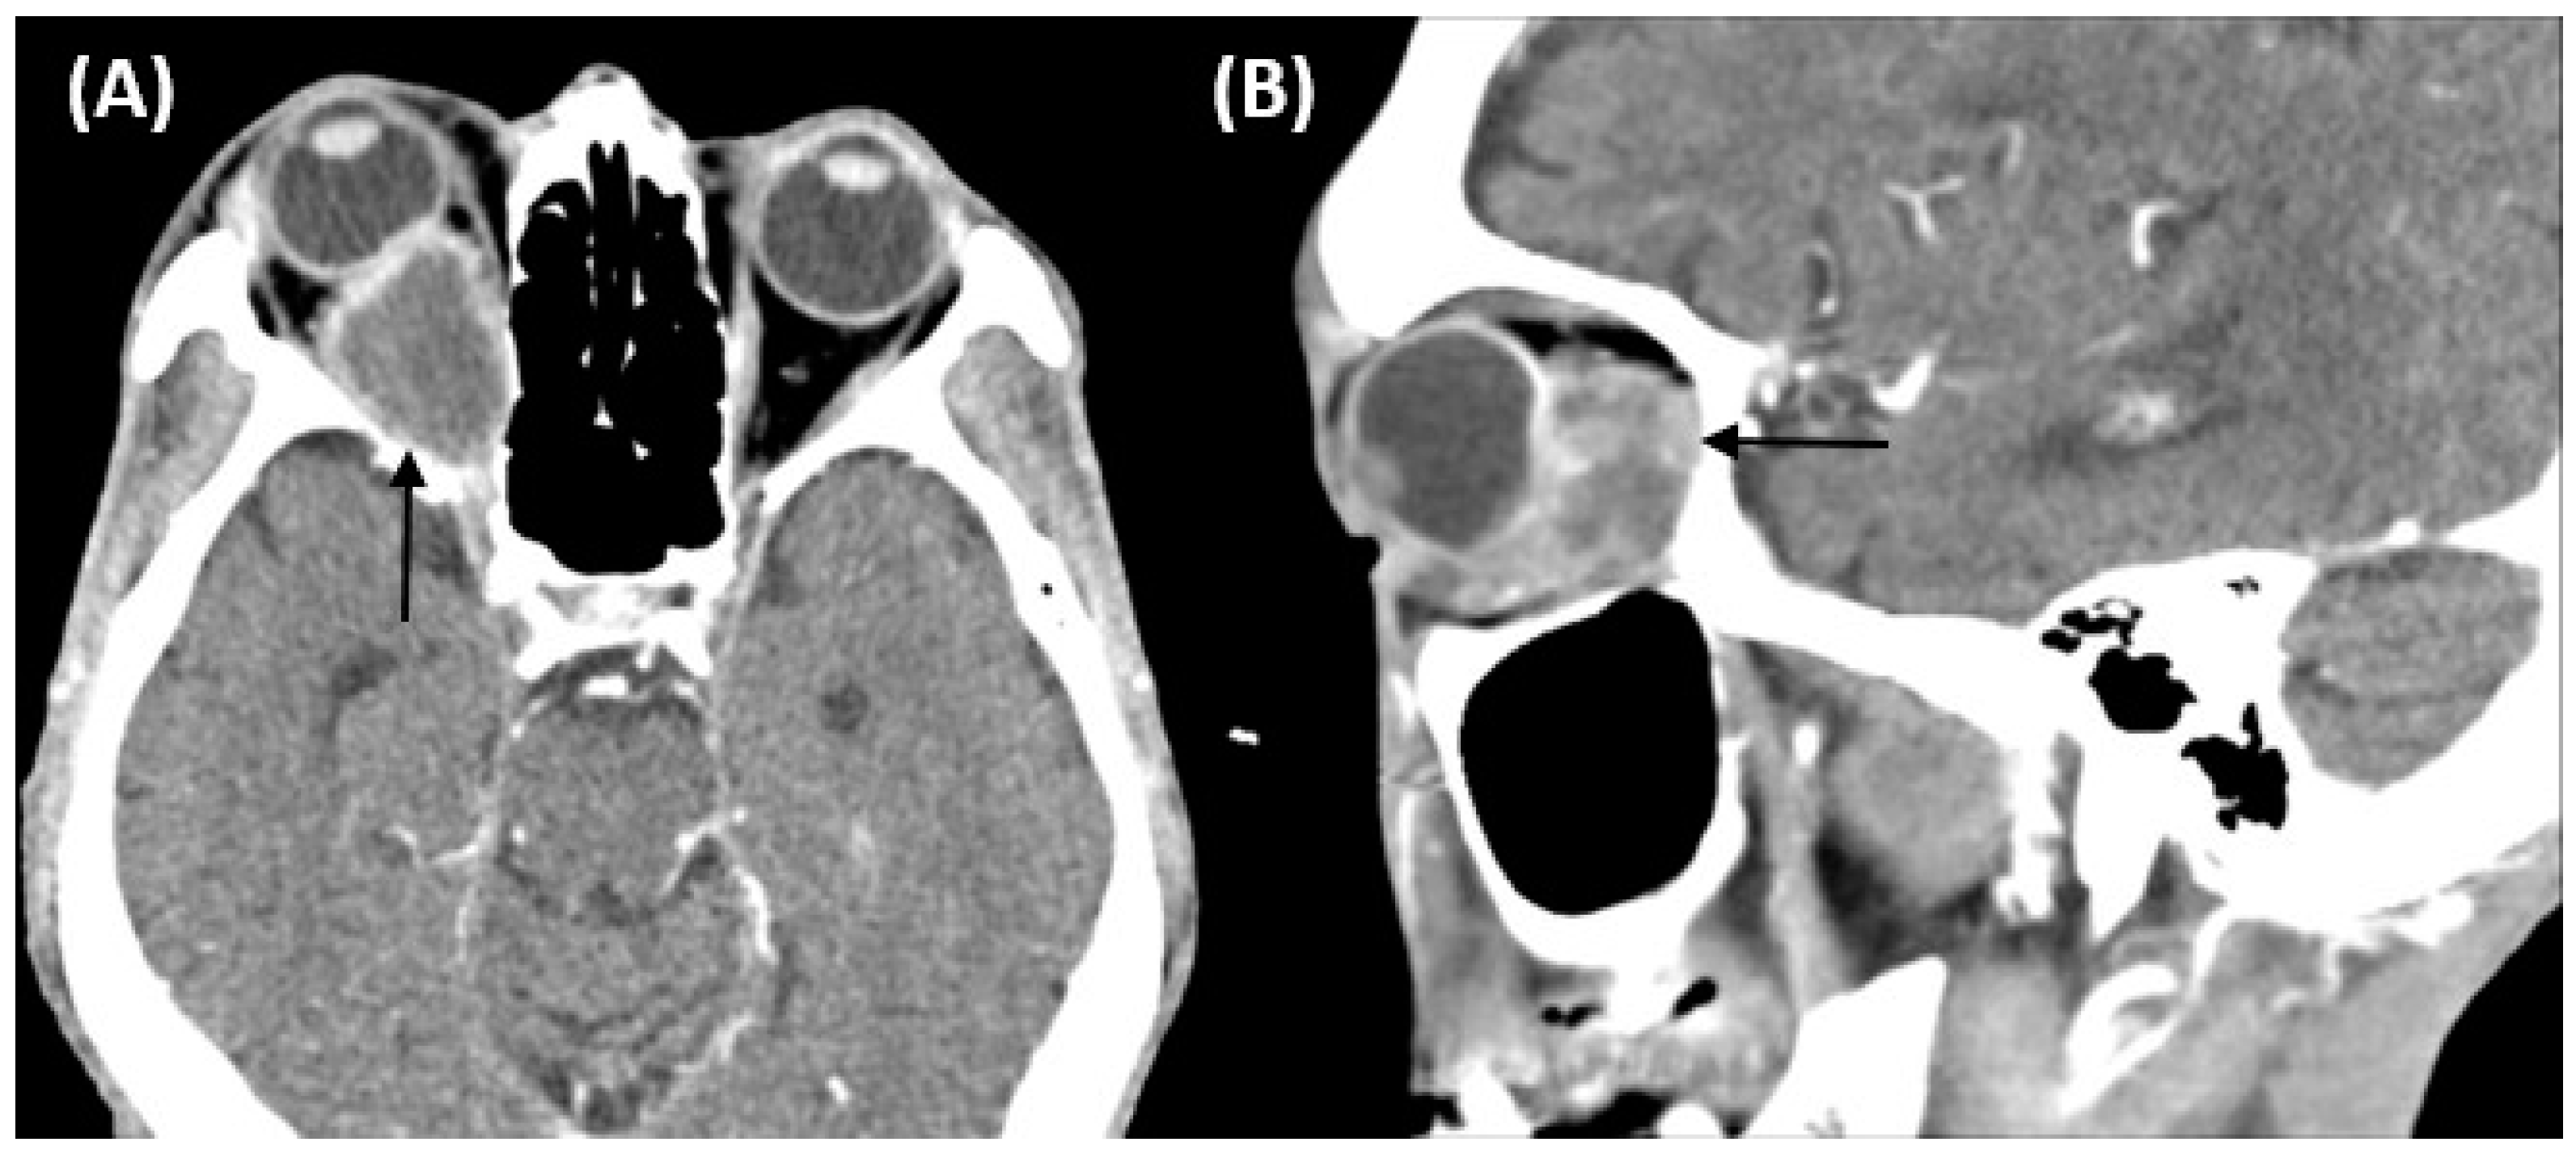

2. Case Report